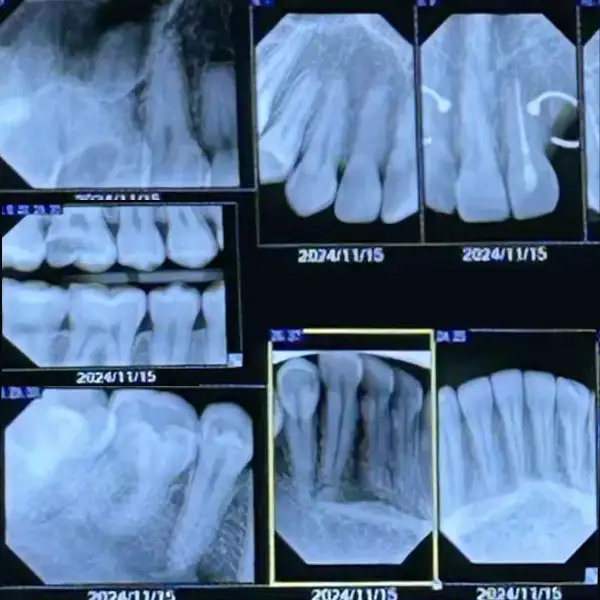

1. Dental Checkup with Digital X-Ray

A comprehensive oral examination to assess teeth, gums, bite, and overall oral health. Using advanced digital X-rays, hidden problems such as cavities, infections, bone loss, and impacted teeth can be detected at a very early stage — even before symptoms appear.

Early diagnosis allows for timely and minimally invasive treatment, helping prevent pain, complications, and costly dental procedures in the future. Regular dental checkups play a vital role in maintaining a healthy smile and overall well-being.